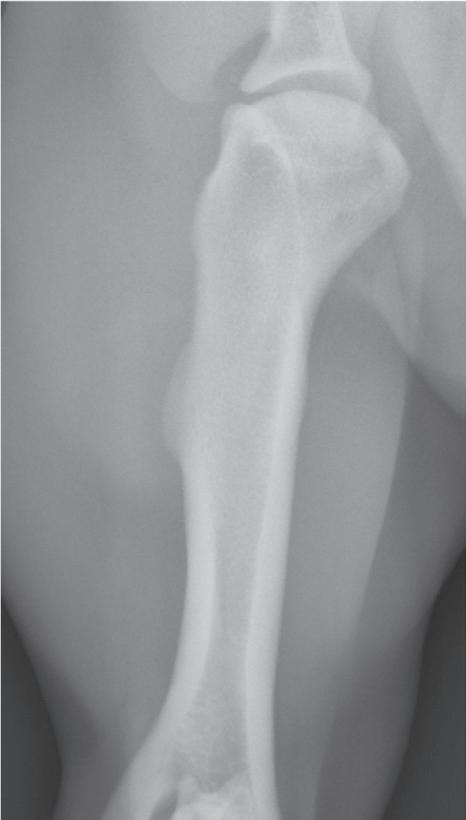

Figure 1-4. Correct orientation of lateral views of two extremities. A lateral view of a humerus (A) and a lateral view of a tarsus/pes (B) are shown here. Note the difference in directional terms depending on whether the part being imaged is above or below the tarsocrural or antebrachiocarpal joint.